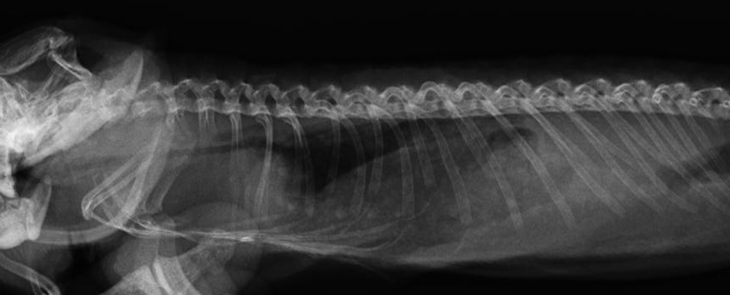

心疾患が疑われる場合、症状の非特異性を克服し、正確な病態を把握するために、画像診断が強く推奨されます。X線撮影は、心臓のシルエットおよび体腔内の配置、また肺野の異常を評価する上で有用です。